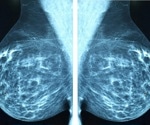

Breast Cancer

Breast cancer is cancer that forms in tissues of the breast, usually the ducts (tubes that carry milk to the nipple) and lobules (glands that make milk). It occurs in both men and women, although male breast cancer is rare.